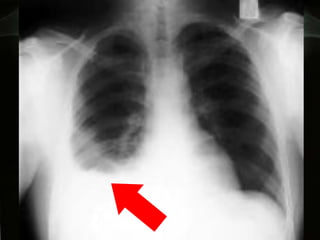

Densa opacidad en base derecha con borramiento del hemidiafragma correspondiente y la parrilla costal

Hemitorax derecho: Derrame pleural Hemitorax Izquierdo: Derrame sub pulmonar

Densa opacidad enbase derecha con borramiento del hemidiafragma correspondiente y la parrilla costal

Hemitorax derecho: Derramepleural Hemitorax Izquierdo: Derrame sub pulmonar